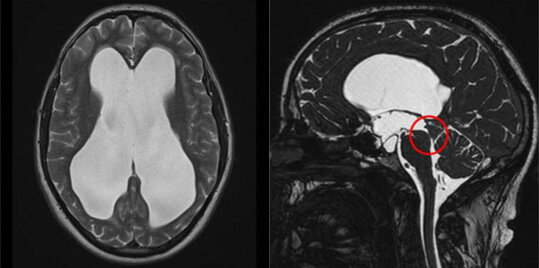

Kommt es zu einer Verlegung der Hirnwasserzirkulation, z. B. durch eine Verengung zwischen der dritten und vierten Hirnwasserkammer (Aquäduktstenose), kann ein sog. Verschlusshydrocephalus (Hydrocephalus occlusus) resultieren. Auch Tumoren innerhalb der Hirnwasserkammern können die Abflusswege verlegen und zu einem Verschlusshydrocephalus führen. Bei diesen Formen des Hydrocephalus kann durch eine ETV eine Verbindung zwischen dem III. Ventrikel und den äußeren Liquorräumen geschaffen werden. Hierbei wird über ein kleines Bohrloch im Schädelknochen ein Endoskop bis in den III. Ventrikel eingeführt und dessen Boden durch eine Perforation zu den äußeren Liquorräumen (basale Zisternen) gefenstert. Dadurch kann ein ungehinderter Liquorfluss unter Umgehung des Hindernisses ermöglicht werden.

Links: Darstellung der deutlich erweiterten Seitenventrikel. Rechts: Darstellung der Aquäduktstenose.